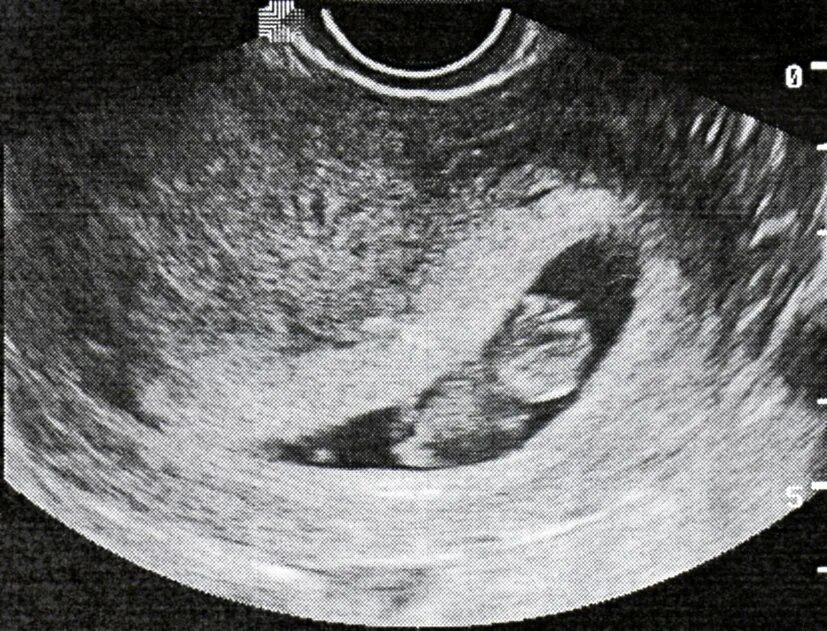

Плодное яйцо и эмбрион форум